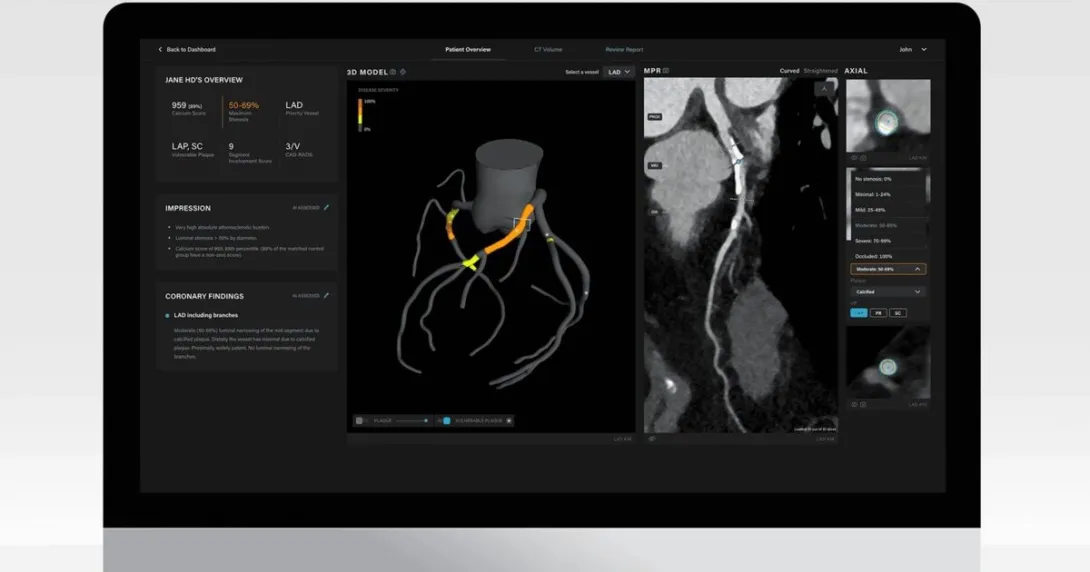

Salix detects and assesses atherosclerotic plaque – a substrate of most heart attacks – in a patient’s arteries as seen in their cardiac CT scans. Using AI, it quickly produces a patient's 3D heart image and a report detailing an assessment of their vulnerable plaque, stenosis, calcium score and total plaque burden within 15 minutes.

Artrya's Salix refers clinicians to high-risk results so they can triage patients early and determine who requires aggressive treatment to prevent the likelihood of a major adverse cardiac event.

"Salix unlocks the capability to triage patients into risk categories, identifying those patients who require further clinical assessments and those who can be reassured. Importantly, Salix will provide clinicians with the best available technology allowing them to spend more time with patients and therefore ensuring better outcomes. It will also improve workflow at radiology practices and make cardiac CT scan reporting more efficient and accurate," Artrya Chief Medical Officer Girish Dwivedi said.

"From the time a scan is completed, within a few minutes I can select the patient of highest interest, and all the vessels are tracked; lesions are identified and assessed; the calcium score is calculated; and a report is written – all before I touch the keyboard," Dr Lawrence Dembo, a cardiologist from Envision Medical Imaging, attested.